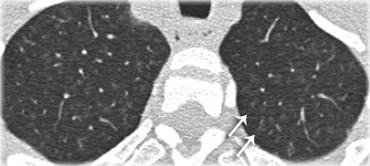

Bên trái là bệnh nhân nữ 47 tuổi với triệu chứng ho khan, khó thở nhẹ và xét nghiệm máu bình thường.

Bệnh nhân được chụp X-quang ngực và điều trị kháng sinh.

Phim kiểm tra được chụp lại do bệnh nhân không cải thiện.

Phim X-quang ngực đầu tiên cho thấy đông đặc hai bên ở thùy dưới (mũi tên), ban đầu được diễn giải là nhiễm trùng.

Sau hai tuần điều trị kháng sinh, không có cải thiện.

Chẩn đoán phân biệt lúc này bao gồm u ác tính (ung thư phế quản phế nang hoặc u lympho), viêm phổi tăng bạch cầu ái toan, viêm phổi tổ chức hóa, bệnh Wegener hoặc một thể không điển hình của sarcoidosis.

Tiếp tục với hình ảnh HRCT.

Hãy cuộn qua các hình ảnh bên trái.

Có nhiều vùng đông đặc.

Các dấu hiệu kèm theo bao gồm hạch to rốn phổi và trung thất.

Chẩn đoán phân biệt trên hình ảnh CT về cơ bản giống như trên X-quang ngực.

Kết quả mô bệnh học xác nhận sarcoidosis phế nang.

Chỉ có một gợi ý duy nhất cho chẩn đoán, đó là sự hiện diện của các nốt nhỏ có thể nhận thấy ở hình 3, nhưng rất khó quan sát.

Trường hợp này minh họa rõ ràng rằng sarcoidosis thực sự là “kẻ bắt chước vĩ đại”.

Do đó, sarcoidosis cần được đưa vào danh sách chẩn đoán phân biệt của chúng ta!